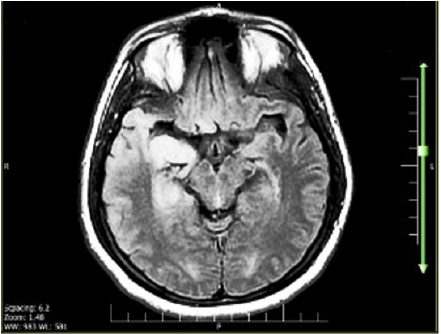

Gradually, her level of mental status started to impair. She occasionally showed symptoms of seizure, confusion, drowsiness and blurred vision and her fever continued as well. Antiepileptic medicine (Phenytoin) was promptly started to abort seizure. Neurology and infectious consultation were requested. Urgent Computerized

Tomography scan (CT) was normal; however Magnetic Resonance

Imaging (MRI) was shown hyperintensity in the temporal lobe

given that MRI showed hyperintensity region in the temporal lobe

as well, antibiotic therapy ceased, and Acyclovir and Phenytoin

Figure 1: Temporal lobe hyperintensity in patient with Herpes Simplex Virus type-1 encephalitis.

diagnosis needs paraclinical tools such as MRI that present a

maximum sensitive and specific neuroimaging document. Usually,

as soon as the HSE clinical presentation occur, MRI show edema or

hypersignal changes in the temporal lobe [7]. Regarding detected

hyperintensity in our patient’s temporal lobe and 80% Lymph in

the CSF, a high degree of clinical suspicion for herpes encephalitis